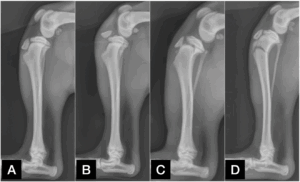

Common types of fractures near the growth plate of the tibia in young dogs include:

• Tibial tuberosity avulsion fractures, where a small piece of bone (the tibial tuberosity) gets pulled off (Figure 1B)

• Proximal tibial physeal fractures, which involve the main growth plate of the tibia (Figure 1C)

• Proximal tibial metaphyseal fractures, involving a bigger part of bone lower than the growth plate (Figure 1D)